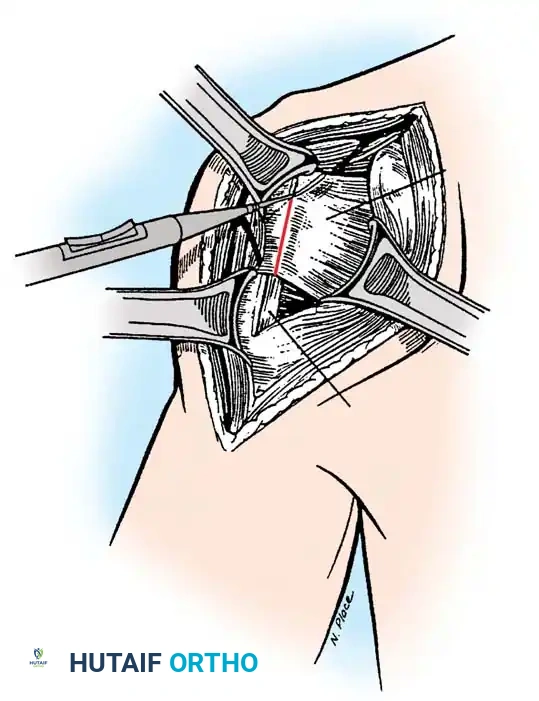

The subscapularis is the gatekeeper to the joint. It can be managed via a tenotomy (1 cm medial to the lesser tuberosity), a lesser tuberosity osteotomy (LTO), or a subscapularis peel. LTO provides superior bone-to-bone healing and is increasingly favored.

Securely repair the subscapularis using heavy non-absorbable sutures through transosseous tunnels.